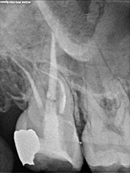

Root Canal Cases